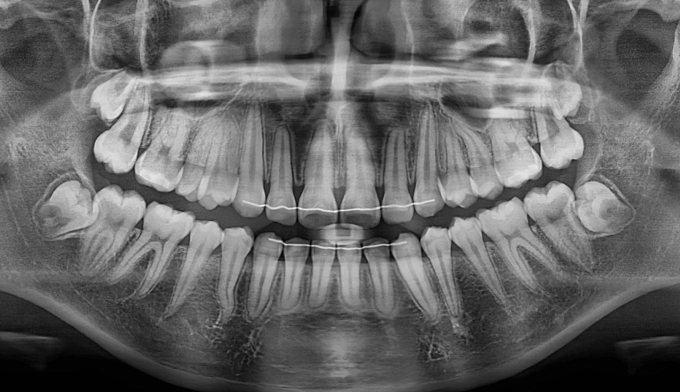

공간이 부족하므로 먼저 양쪽으로 치아를 벌려 공간을 확보해준 후 겹쳐진 치아들을 배열해줍니다.

치아 배열 중 앞니가 뻐드러지지 않게 조심합니다.

총 치료기간은 20개월입니다.